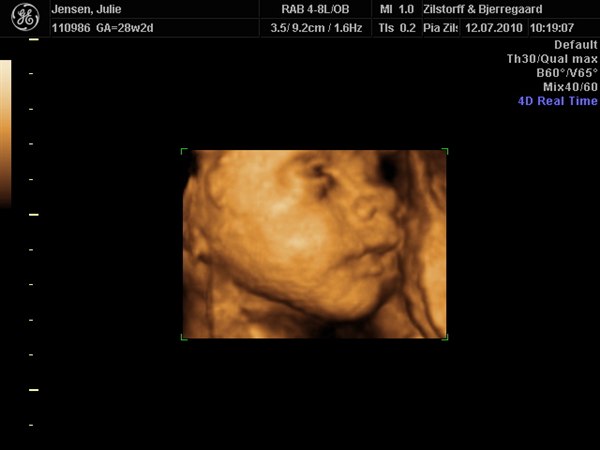

smilehuller og ligner helt sikkert Viktor

Kan slet ikke komme mig over hvor fantastisk det er at se det lille menneske inden i en

Vedhæftede fotos (klik for at se i fuld størrelse)